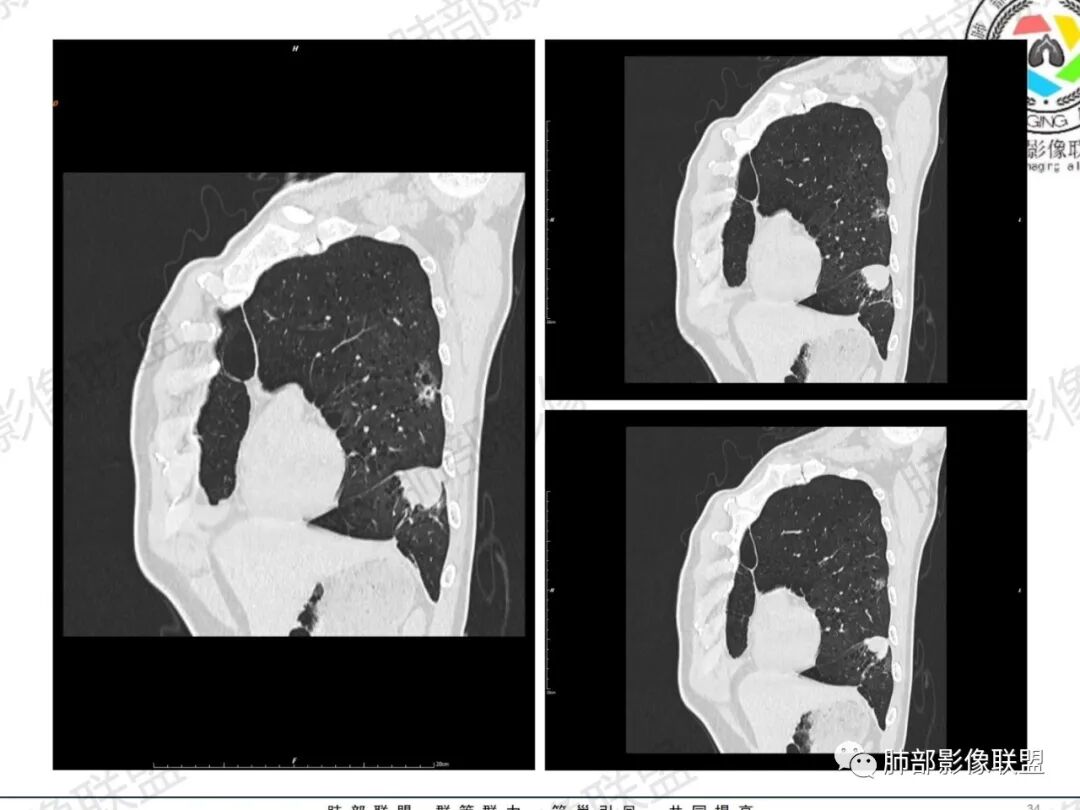

一切∮随缘:左肺下叶不规则肿块,边缘光滑,平直,局部彭隆,分叶,近端支气管堵塞,远端与胸膜相贴,平扫密度尚均匀,增强后不均匀强化,内部可见低密度坏死,胸膜下多发肺气肿,伴双肺散在光滑小结节,实验室肿瘤标志物高,考虑恶性:神经内分泌癌(大细胞),腺癌,鳞癌。

琦遇:恶性没有问题,肺气肿底子、病灶分叶、少许毛刺、叶间胸膜凹陷、部分边缘可见清晰的GGO、胸膜牵拉凹陷、局部胸水、近端支气管截断、部分支气管被推移、占位效应明显、强化特点为不均匀强化、内部有少许沼泽样低强化区,强化部分轻中强化为主、余肺可见转移性结节、左肺上叶似为囊腔型腺癌一枚,肿瘤标志物提示非小、神经内分泌,综合分析考虑大神泌、腺癌、腺鳞癌、鳞癌  同时左肺上叶囊腔型腺癌  肺转移

蕊:中老年男性,吸烟史,肺气肿背景,左肺上叶类圆形肿块影,边界清晰,边缘凹凸不平,有分叶,支气管进入阻断,临近胸膜栽赃,整体病灶膨隆,局部周围可以清晰ggo,临近叶间裂内凹,轻度强化,并可见多个低密度区,坏死可能,界线不清;肺内多结节,边缘光滑,考虑恶性伴转移,鳞癌、腺癌

傅昌瑜:中老年男性,肺气肿背景,右胸背疼痛1周。CEA、NSE、CYFRA—211升高。左上肺混合磨玻璃结节,内见较多空泡和扩张支气管。左下肺胸膜下肿块,边缘较光滑,深分叶,似有血管进入,与支气管关系不清,内见不均匀强化,见沼泽地样坏死,有胸膜栽赃。另两肺多发圆形小结节。考虑恶性并肺内转移,多原发可能性大,左上肺腺癌,左下肺病理难以判断,小细胞癌?鳞癌?

小锁:中老年男性,肺气肿背景,右胸背疼痛1周。CEA、NSE、CYFRA—211升高。左上肺混合磨玻璃结节,边界清楚,内见较多空泡。左下肺肿块,边缘清楚,深分叶,有血管和支气管进入,胸膜凹陷。另两肺多发圆形小结节。考虑双发原位癌,左上肺腺癌,左下肺大神泌或腺鳞癌可能,肺内转移。

蓝天白云:中年男性,肺气肿背景,左肺下叶肿块,边缘膨隆,有分叶,内有湖泊样坏死,有轻中度强化,局部胸膜栽赃,收缩力不强,周围见肺气肿征象。左肺上叶混合磨玻璃影,边界清楚,考虑都是恶性,左上肺iac,左下肺腺鳞癌,或大细胞肺癌可能。两肺多发结节,考虑转移

LCNEC最常见的影像特征包括:(1)肿块发生部位:周围型肺癌为主,少数发生于肺中央。(2)肿块大小及形态。因肿瘤细胞生长迅速常形成较大肿块,因此其体积一般较大,直径常在3~10cm范围内,病灶常为不规则形软组织肿块。(3)肿块边界。多数学者报道大多数肿块边界清晰,边缘呈分叶状,毛刺征及“胸膜凹陷征”少见,认为与该病对周围组织浸润较轻及较少产生纤维瘢痕组织牵拉有关联。(4)肿块密度、强化特点及代谢情况。据文献报道,该类肿瘤因体积较大CT上常见软组织肿块,且多数密度不均匀,内见囊变坏死区,增强后呈轻或中度不均匀强化(可见强化者占75.7%),认为其强化特点与其内部肉眼可见坏死灶和肿瘤较大直径有关。(5)伴随症状及远处转移。该病恶性程度高,侵袭性强,常侵犯邻近结构,如胸膜、心包、邻近骨质或纵隔内组织等,易出现纵隔淋巴结转移,部分发生肺内及远处转移,少数早期可出现广泛远处转移。